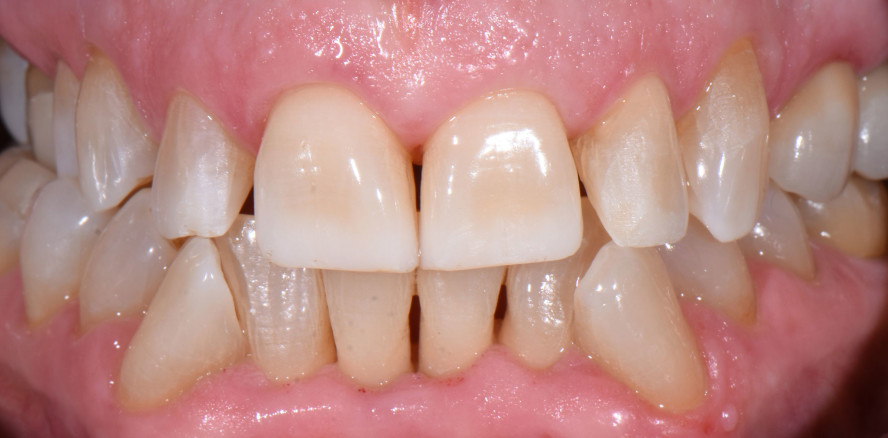

Direkte Frontzahnrestaurationen sind zeitaufwendig und ihr Ergebnis hängt in hohem Maße von der Erfahrung und Geschicklichkeit des Zahnarztes...

Direkte Frontzahnrestaurationen sind zeitaufwendig und ihr Ergebnis hängt in hohem Maße von...

Die langfristig erfolgreiche Rekonstruktion einer ganzen Frontzahnkrone mit Komposit erfordert einige mechanische Überlegungen zur Anwendung...

Die langfristig erfolgreiche Rekonstruktion einer ganzen Frontzahnkrone mit Komposit erfordert...